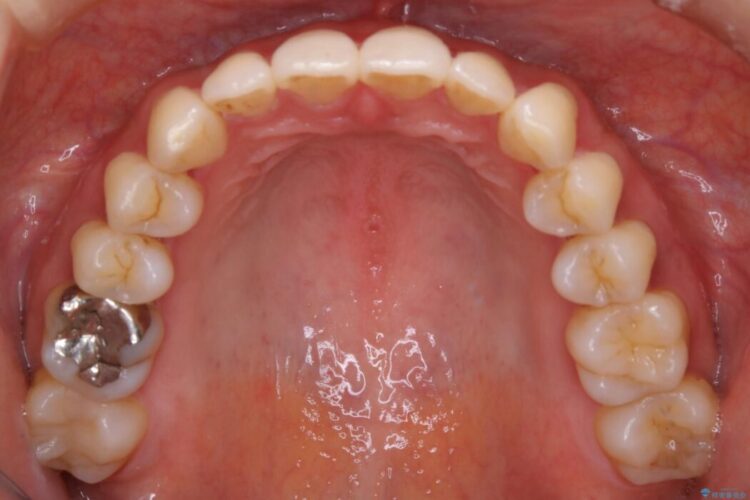

検査したところ歯の叢生自体は歯列幅の拡大やディスキング(IPR)で解決できる範囲内でした。

ですが、上顎左側の歯が前方へ寄っている状態であるため噛み合わせにズレが生じていました。

よって噛み合わせのズレをマイクロインプラントを使用して歯を移動させ、インビザラインにて歯列の整えを行うこととしました。